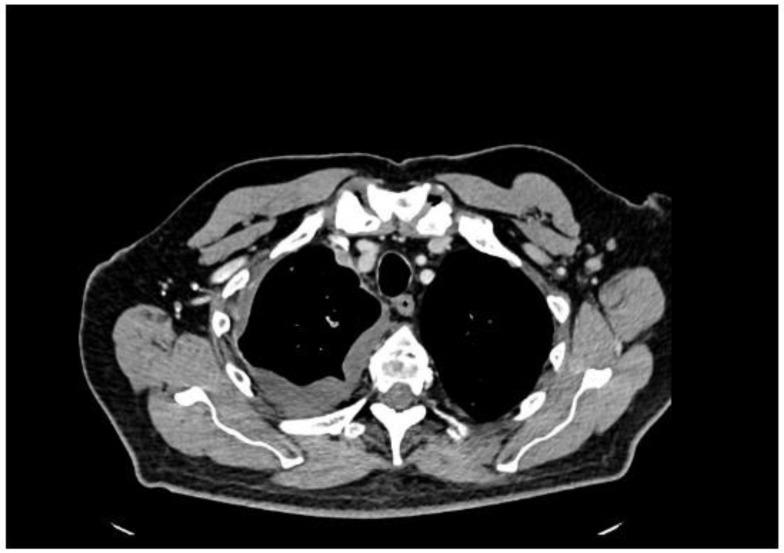

我们描述了一名77岁男性,他出现劳力性呼吸困难和间歇性咳嗽,最初提示心肺病因。影像学检查发现多个胸膜结节和广泛的右侧胸腔积液。尽管血清前列腺特异性抗原(PSA)水平临界为2.91 ng/mL,但胸膜活检的组织病理学和免疫组化结果证实为转移性前列腺腺癌。随后的影像学检查在前列腺中发现了一个PI-RADS 5类病变,活检证实为ISUP 5级组疾病(Gleason评分4 + 5 = 9)。骨扫描显示无骨转移,腹部增强CT未发现其他转移病灶。患者开始接受雄激素剥夺治疗,随后使用阿比特龙。该病例强调了前列腺癌非典型转移表现所带来的诊断挑战。低或中度升高的PSA可能会掩盖对前列腺起源的怀疑,尤其是对于提示间皮瘤的胸膜病变。包括雄激素受体、AMACR和Prostein在内的免疫组化标志物对于准确诊断至关重要。